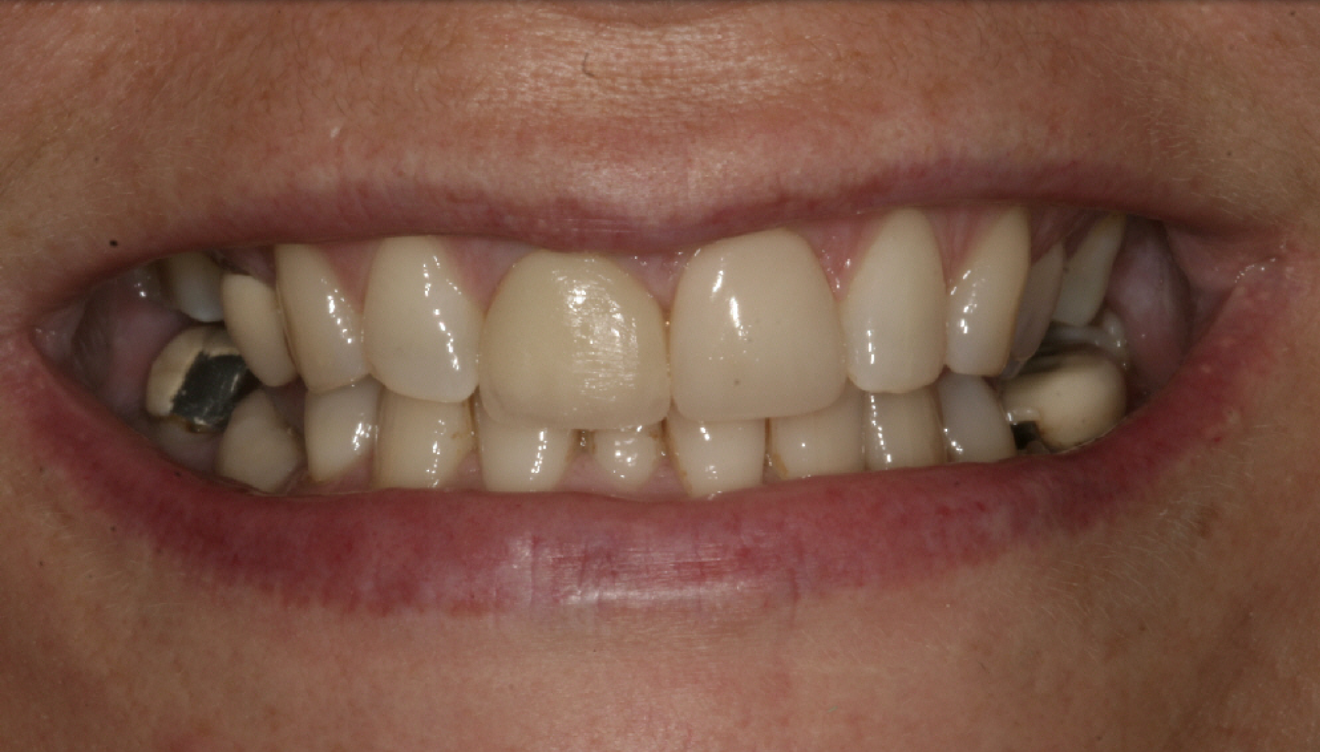

The following case highlights the treatment of a patient over 17 years. With simple orthodontics, direct edge bonding applied according to the Dahl principle and a little maintenance, the patient’s teeth were prevented from becoming worse at a relatively low cost.

This case effectively demonstrates that the concept of “pausative” dentistry can be aesthetic, functional and affordable. If this patient’s teeth had been left untreated from 2004, how would they have looked 17 years later? The mandibular crowding would likely have worsened.2 The bite would probably have deepened, causing more surface loss, as there were already signs of dentine exposure. The already reduced posterior guidance would likely have worsened and more posterior teeth may have failed.

The “pausative” approach with alignment and direct edge bonding according to the Dahl principle can help to minimise the amount of damage in long-term cases (Fig. 16). It can help prevent further tooth surface loss and tooth positional changes and hold the occlusion in a much better position over time.

Fig. 16: 2021—the patient’s teeth 17 years later thanks to interceptive treatment with alignment and direct edge bonding according to the Dahl principle to minimise the amount of damage.